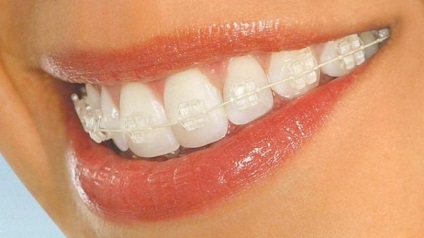

Kerámia merevítők képek előtt és a telepítés után

Kerámia rögzítő rendszer a fotón szinte lehetetlen megállapítani, kivéve, ha végzett akcentusa.

Most használja és kerámia konzolok és egy fehér arc a képen azok könnyen azonosítani, és átlátható. Maguk az elemek is fehér és átlátszó. Ítélve a fotók a fehér nadrágtartó is lehet feltűnő, mint átlátszó. Ez egy új szót a technológia, de a telepítési folyamat ugyanaz, mint az összes többi hasonló rendszerek. Minden konzol beszerelni a helyére jelölések szerint. Rögzítése az ív révén keletkezett lekötést vagy kapoccsal.